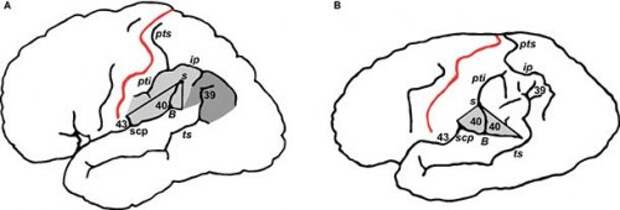

2. Одна из частей мозга Эйнштейна была на 15% больше, чем у среднестатистических людей

Когда исследователи изучили мозг одного из самых гениальных мыслителей 20 века, Альберта Эйнштейна, они обнаружили, что его нижняя теменная доля была на 15% крупнее, чем у обычных людей. Некоторые ученые полагают, что именно эта аномалия и ответственна за его высокий уровень интеллекта и математические таланты.